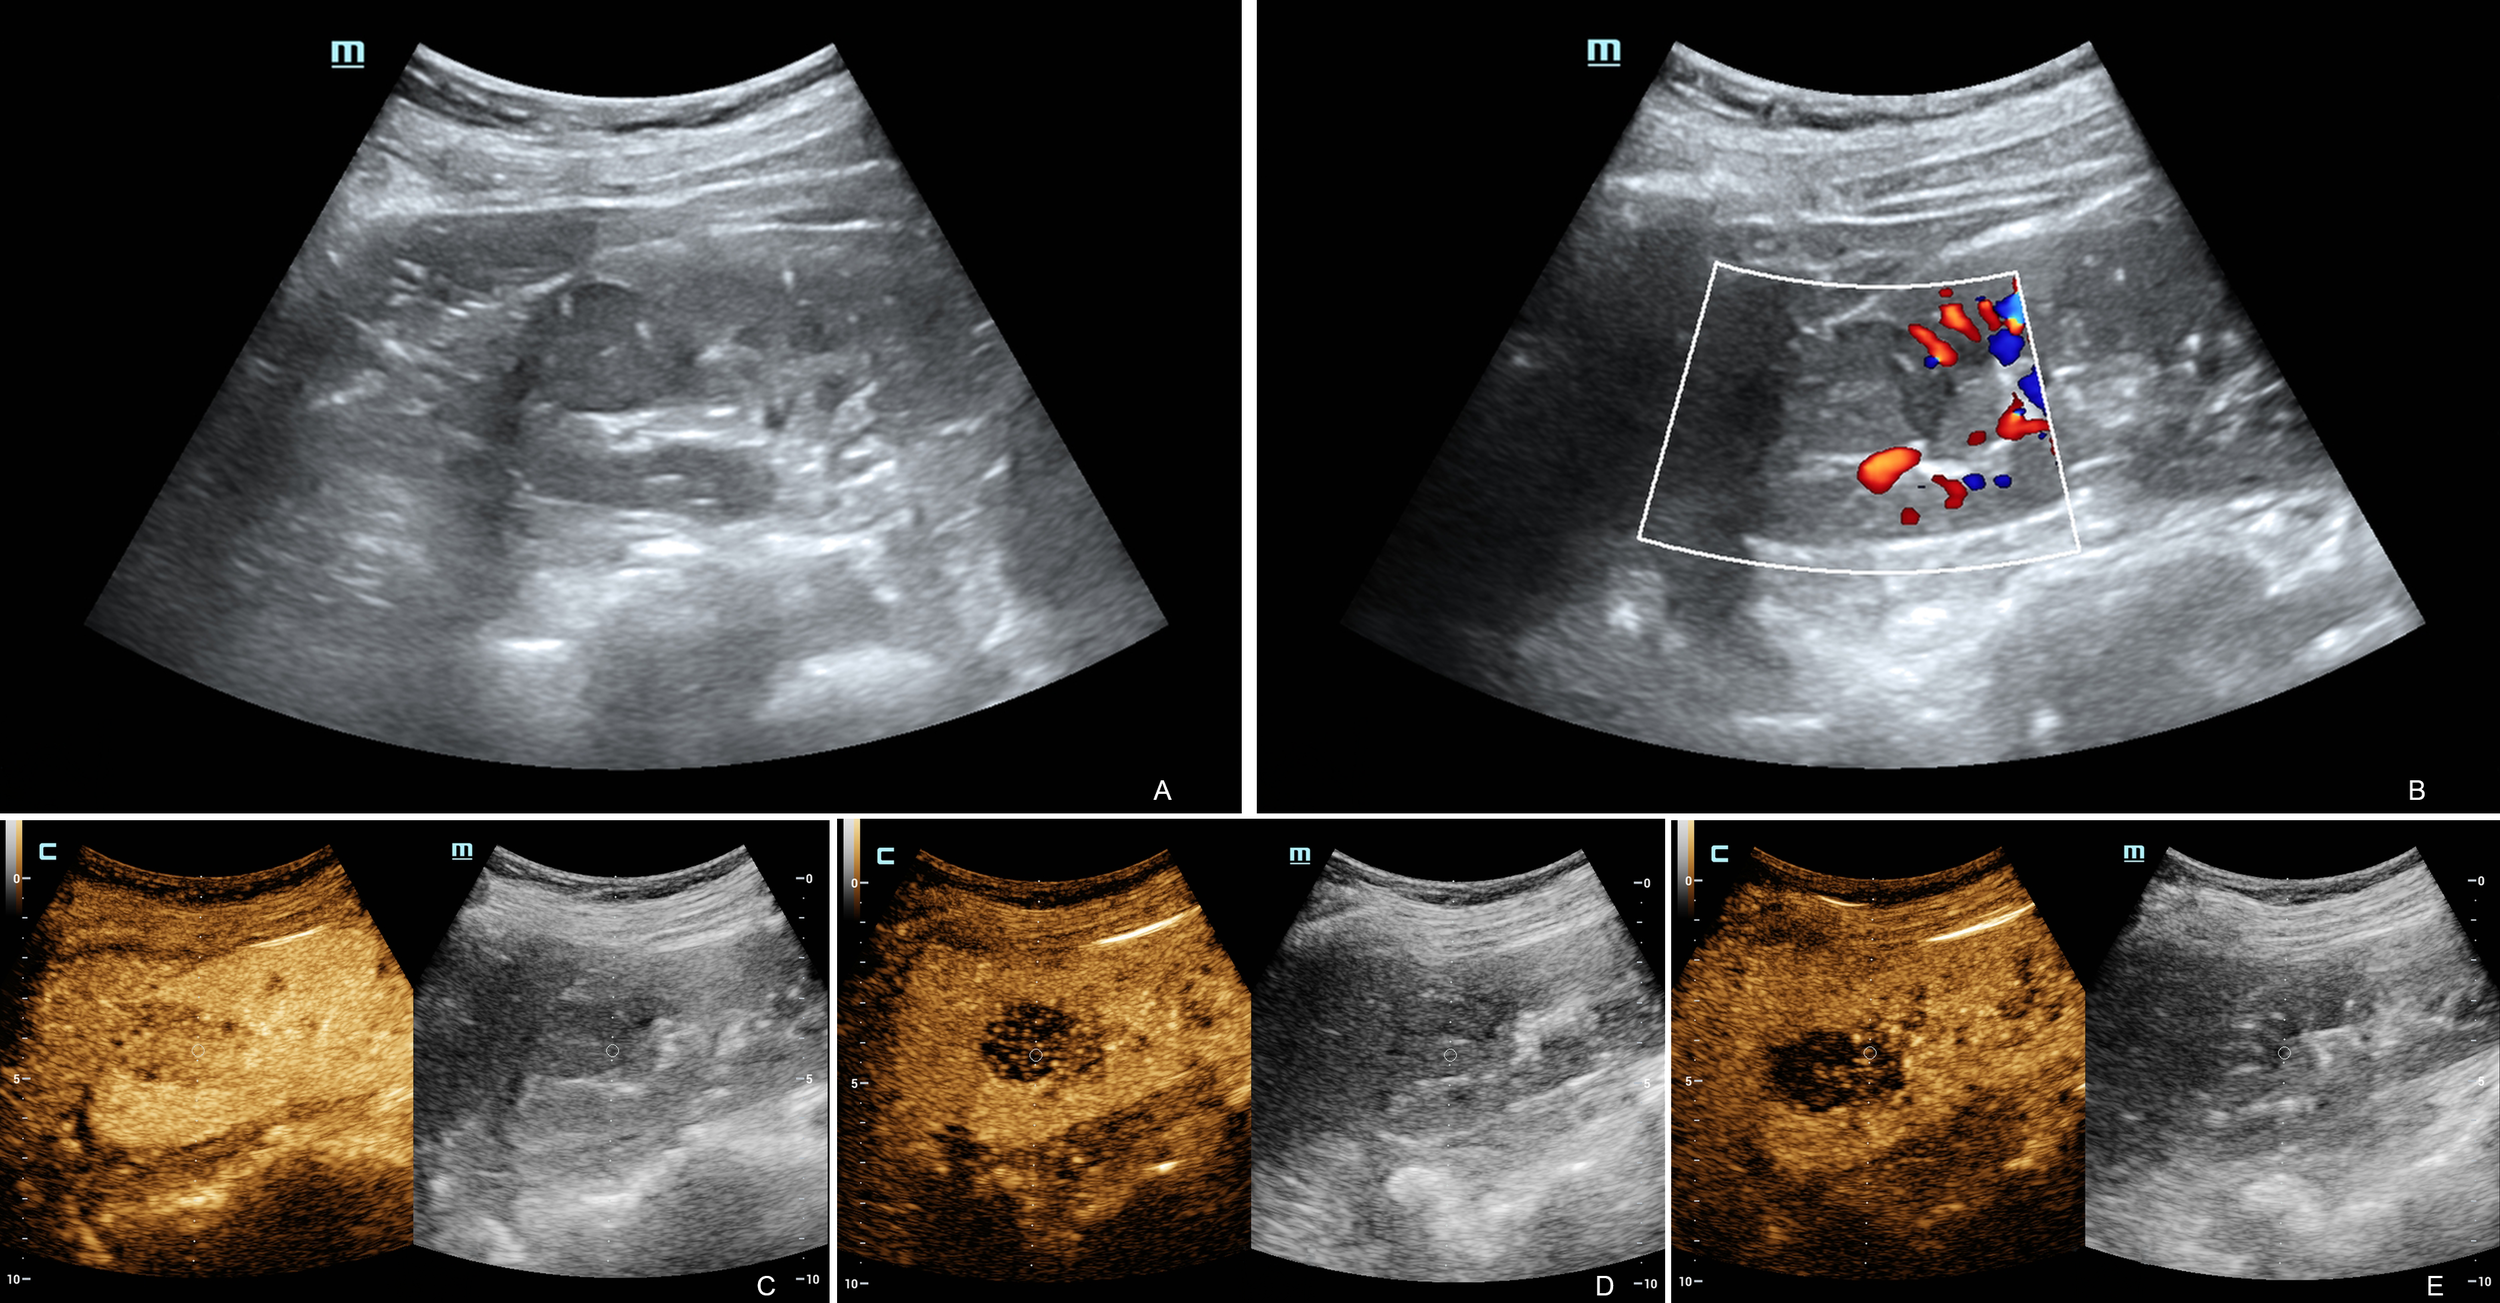

Eight patients underwent conventional abdominal ultrasound and CDFI. Three patients underwent conventional ultrasound, CDFI and CEUS. Most of the lesions (10/11) were located in the renal cortex and showed clear boundaries and regular shapes (Figure 1A). The only lesion left was located in the cortex-medullary junction and showed a fuzzy boundary and irregular shape on conventional ultrasound. Only one case showed calcification within the lesion. Another case displayed an acoustic halo. Using renal parenchymal echo as a reference, the grayscale ultrasound image demonstrated that most of the lesions (9/11) were homogeneously hypoechoic. One case was homogeneously isoechoic, and the only lesion left was heterogeneously hypoechoic. In CDFI, 3 cases showed internal dotted or linear blood flow signals, and 8 cases showed no internal blood flow signal (Figure 1B). Six cases showed peripheral dotted blood flow and there was no obvious peripheral blood flow signal around the masses in the other five cases. CEUS imaging studies were completed successfully in 3 patients with satisfactory imaging quality. In the cortical phase, three lesions showed mild enhancement. All of their enhancement was rather heterogeneous and later than that of the adjacent renal cortex. In the medullary phase, the washout of the tumors was earlier (2/3) or simultaneous (1/3) than that of the adjacent renal parenchyma. Three lesions showed hypo-enhancement during the delayed phase (Figures 1C-E). Tumors displayed no cystic degeneration in conventional abdominal ultrasound and CEUS. The ultrasound characteristics of the tumors are summarized in Table 2. Of the 11 patients who underwent routine ultrasound, 8 lesions were reported only solid renal tumors on ultrasound and 3 were suspected of renal malignancy. Of the 3 patients who underwent CEUS, two lesions were suspected to be RCC, and one only was reported malignant renal tumors without further diagnosis of the tumors.

Figure 1

Ultrasound and contrast-enhanced ultrasound images of MTSCC. Ultrasound image showing a homogenous mass in the upper pole of the right kidney (A). Color Doppler ultrasound showed no obvious blood flow in the mass, but there was some around it (B). CEUS showed heterogeneous mild enhancement in the MTSCC lesion compared to the adjacent renal parenchyma in the cortical phase (C). In the medullary phase (D), the washout of the tumors was more simultaneous than that of the adjacent renal parenchyma. The lesion showed hypoenhancement during the delayed phase (E). These performances indicated hypovascular renal tumors.